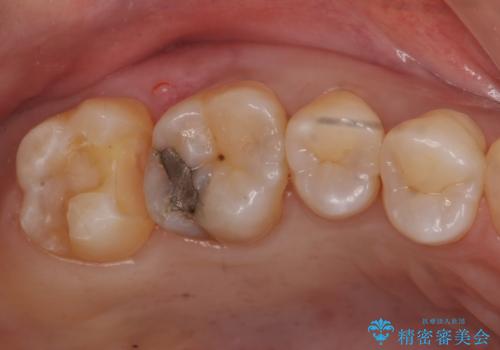

奥歯の虫歯 セラミックインレーによる治療

- 定期検診にて来院、症状はないものの右上の奥歯に虫歯が再発していました。

視診・レントゲン画像より虫歯の大きさを判断し、虫歯の除去後セラミックインレーにて修復することになりました。